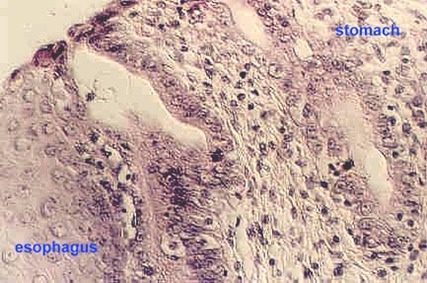

This photo shows the abrupt transition from the stratified squamous (left) of the esophagus to the simple cuboidal epithelium of the stomach. Why are the esophageal glands well placed in the esophagus? Why are they needed?